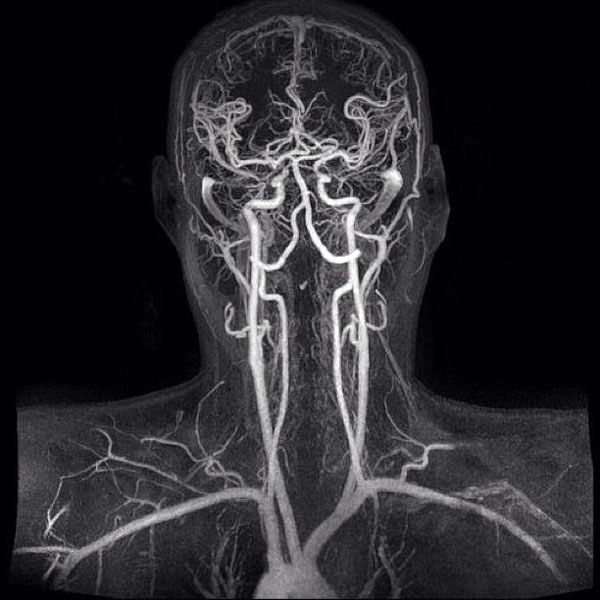

В некоторых случаях для постановки диагноза недостаточно УЗИ, тогда необходимо использовать МРТ сосудов головы и шеи. В основном оно необходимо при наличии постоянных интенсивных головных болей и при подозрении на изменение кровоснабжения некоторых областей мозга вследствие снижения подвижности шейных позвонков. Кроме того, возможно диагностировать тромб, атеросклеротическую бляшку с точной локализацией, стеноз, окклюзию сосуда, его патологическую извитость или изменения диаметра просвета.

МРТ сосудов головы и шеи точнее называется магнитно-резонансная ангиография (МРА). Проведение процедуры основано на введении контрастного вещества внутривенно, благодаря чему обеспечивается визуализация даже наиболее мелких артериол и венул. С появлением МРА возможности врачей расширились в несколько раз, а миллионы людей избавились от многих болезней.